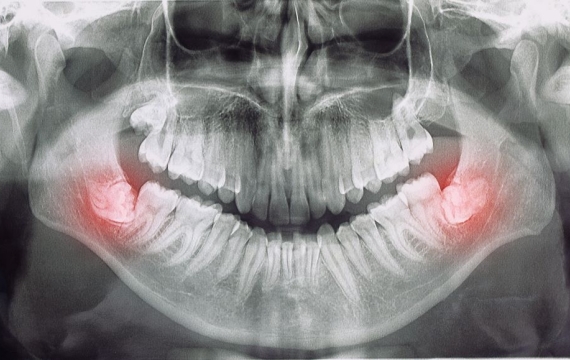

Los cirujanos maxilofaciales pueden tratar una amplia variedad de problemas, desde deformidades faciales hasta lesiones traumáticas y enfermedades dentales complejas. Algunos de los problemas más comunes que se tratan con cirugía maxilofacial incluyen la corrección de mandíbulas desalineadas, la extracción de tumores y quistes, la reconstrucción de huesos faciales dañados y la reparación de paladar hendido.

La cirugía maxilofacial se realiza con anestesia general y puede involucrar la manipulación de huesos, músculos, nervios y otros tejidos blandos. El proceso comienza con una consulta exhaustiva para determinar el mejor plan de tratamiento para el paciente.

Luego, el cirujano maxilofacial realizará la cirugía utilizando herramientas y técnicas especializadas para lograr los mejores resultados posibles. Después de la cirugía, el paciente se someterá a un período de recuperación, que puede durar varias semanas o meses, dependiendo de la complejidad del procedimiento.